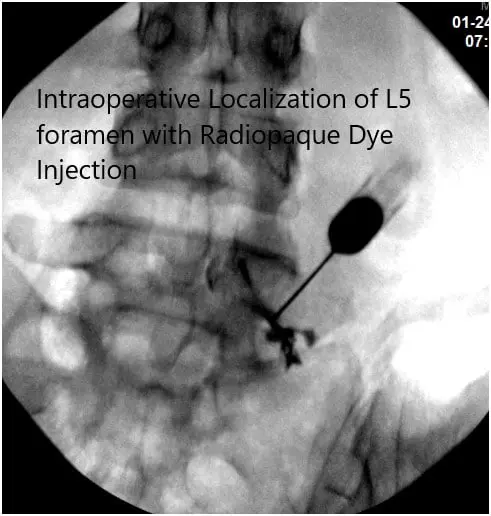

Intraoperative Fluoroscopy Images.

The needle was again re-directed towards the right S1 foramen. It was checked under C-arm and found to be in a satisfactory position. 0.5 cc of Iodine dye was introduced and found to make a good nervogram; 40 mg of Kenalog mixed with 1 cc of 0.5% Marcaine was injected into the right S1 nerve root sheath. The needle was removed. The patient was asked about pain relief and she had near 100% pain relief.